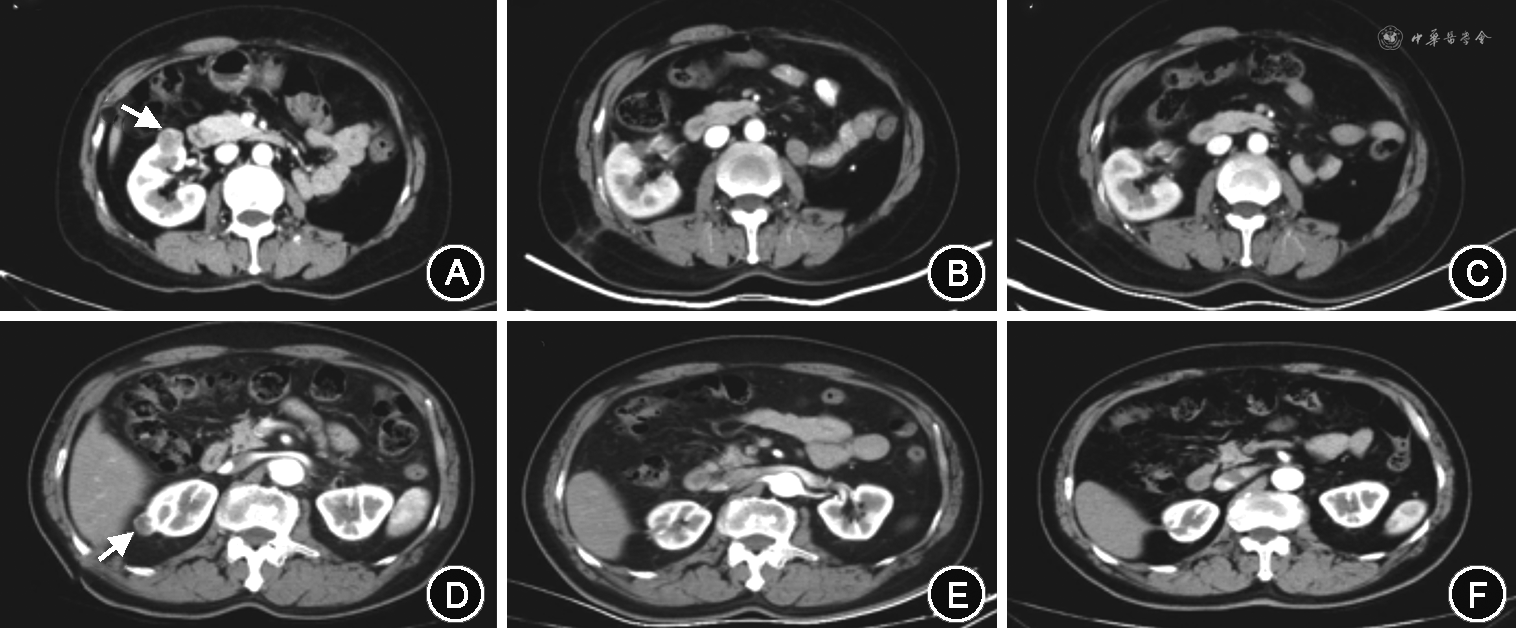

术后中位随访24个月(1~42个月),63例患者存活,2例死亡(1例因心脏疾病,1例因直肠癌转移)。结合术后影像学复查,其他患者均未见肾肿瘤复发和转移征象(图2);定期化验血常规、尿常规及生化全项,结果基本正常。比较因对侧肾肿瘤行根治性切除术后的6例孤立肾患者术前与术后3个月内的肌酐、尿素、尿酸和估算肾小球滤过率(eGFR),差异均无统计学意义(P>0.05),见表1。